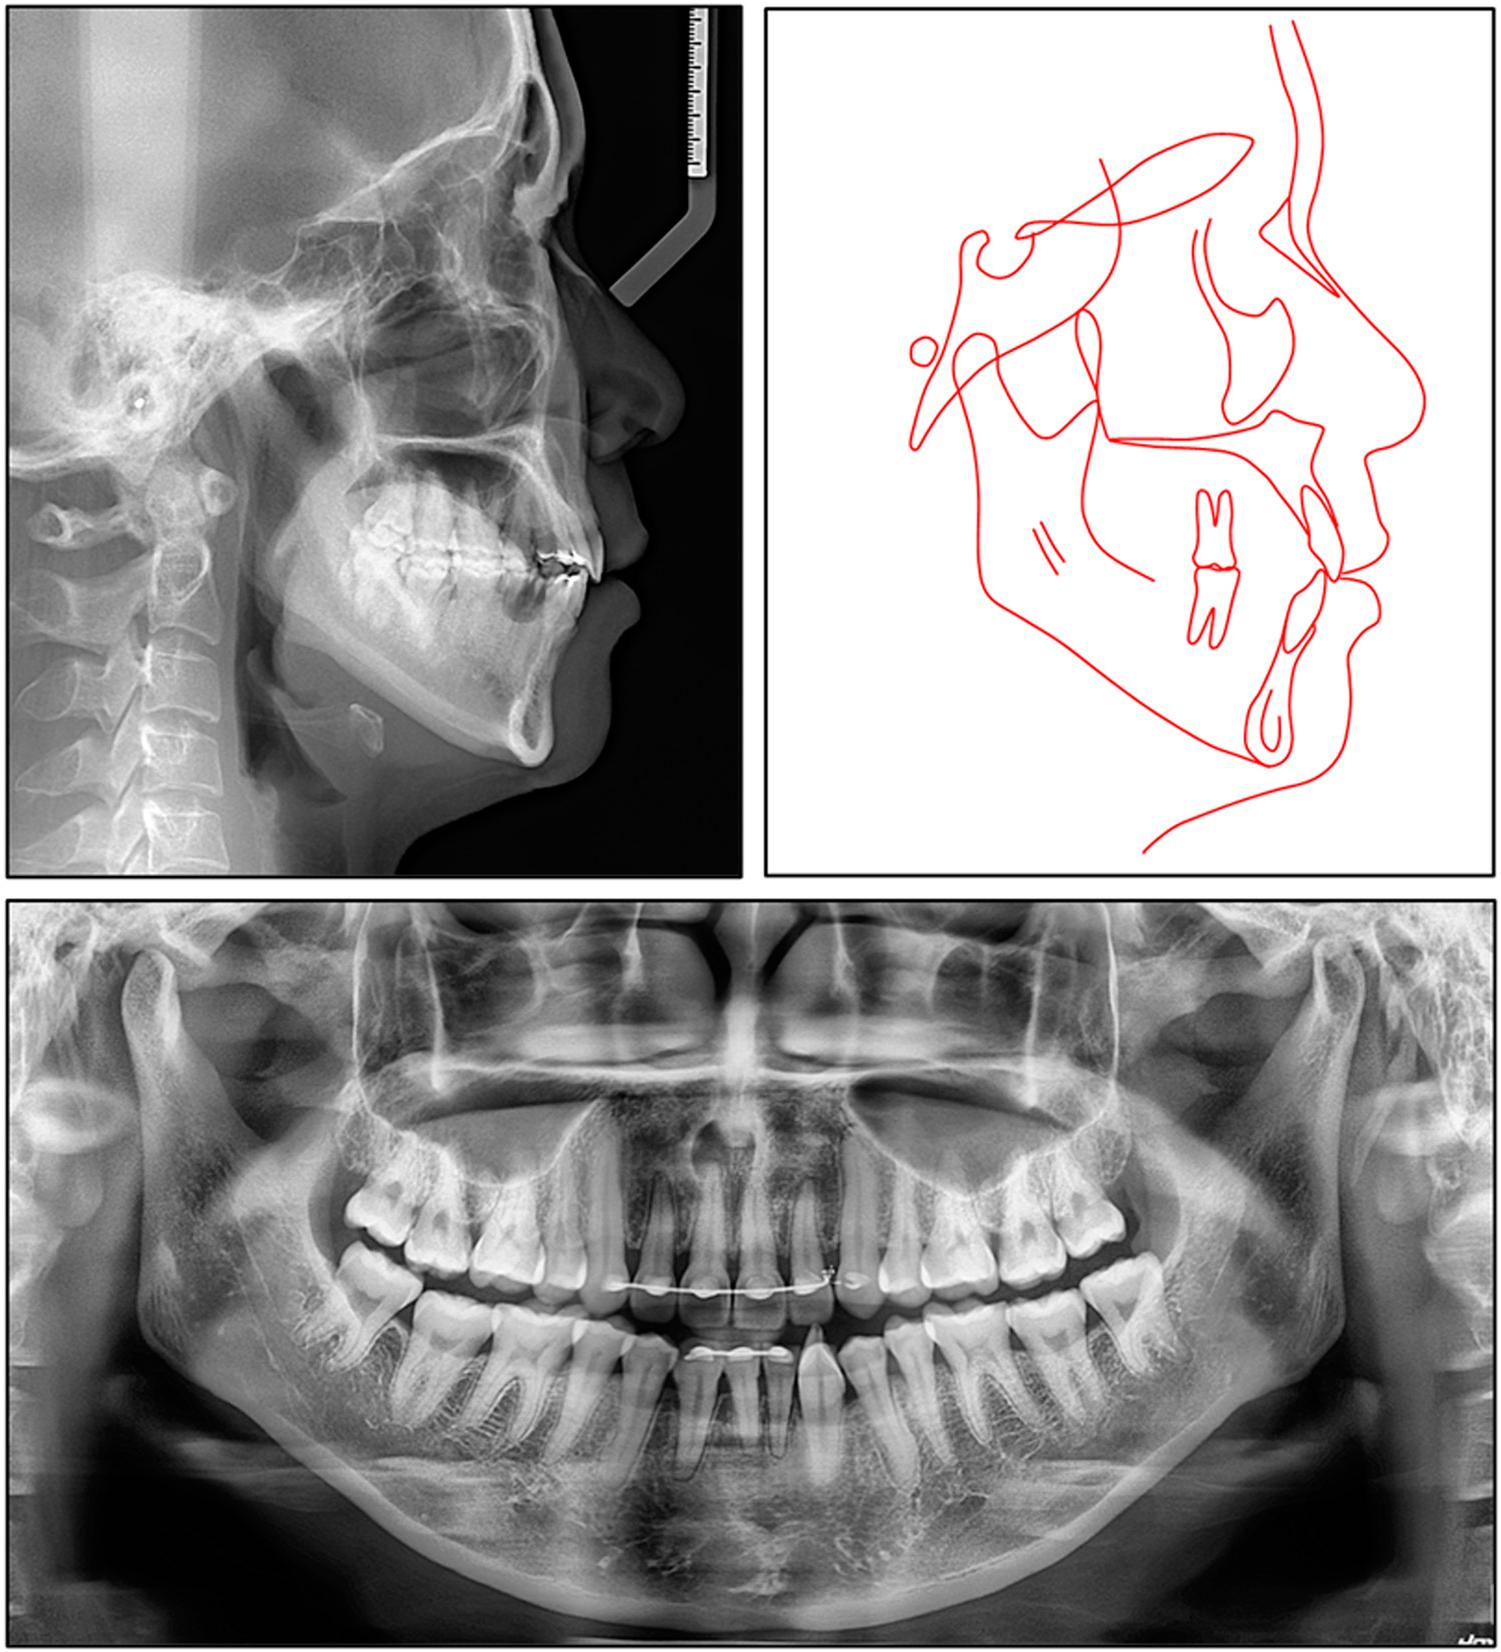

A pretreatment panoramic radiograph confirmed the presence of 30 permanent teeth with normal alveolar bone levels (Figure 3). On the left side, the fused mandibular lateral incisor-canine complex displayed two separate pulp chambers converging into a single root canal, whereas on the right, the corresponding fused tooth exhibited a single pulp chamber and a single root canal.

Pretreatment lateral cephalogram, panoramic radiograph, and tracing.

The lateral cephalogram showed a mild skeletal Class II pattern (SNA, 83.5°; SNB, 79.2°; ANB, 4.4°) with a vertical growth tendency (FMA, 33.9°; Björk sum, 402.5°; gonial angle, 129.1°) (Table I). The sagittal jaw disharmony was minimal (Wits appraisal, -0.2 mm; Pog-to-N perpendicular, -4.5 mm), and the maxilla was positioned slightly anterior to the cranial base (A-N perpendicular, +2.2 mm). The maxillary incisors were proclined and prominent (U1-SN, 106.9°; U1-NA, 23.3°, 7.0 mm), while the mandibular incisors were normally inclined (IMPA, 89.9°; L1-NB, 31.5°, 9.3 mm), generating an interincisal angle of 120.8°. The occlusal plane was steep (cant 8.5°). The overjet was 4.2 mm and overbite 2.6 mm. A soft-tissue analysis confirmed a slightly convex profile with the upper and lower lips 1.4 mm and 2.3 mm, respectively, anterior to the E-plane, while the nasolabial angle measured 86.5°.